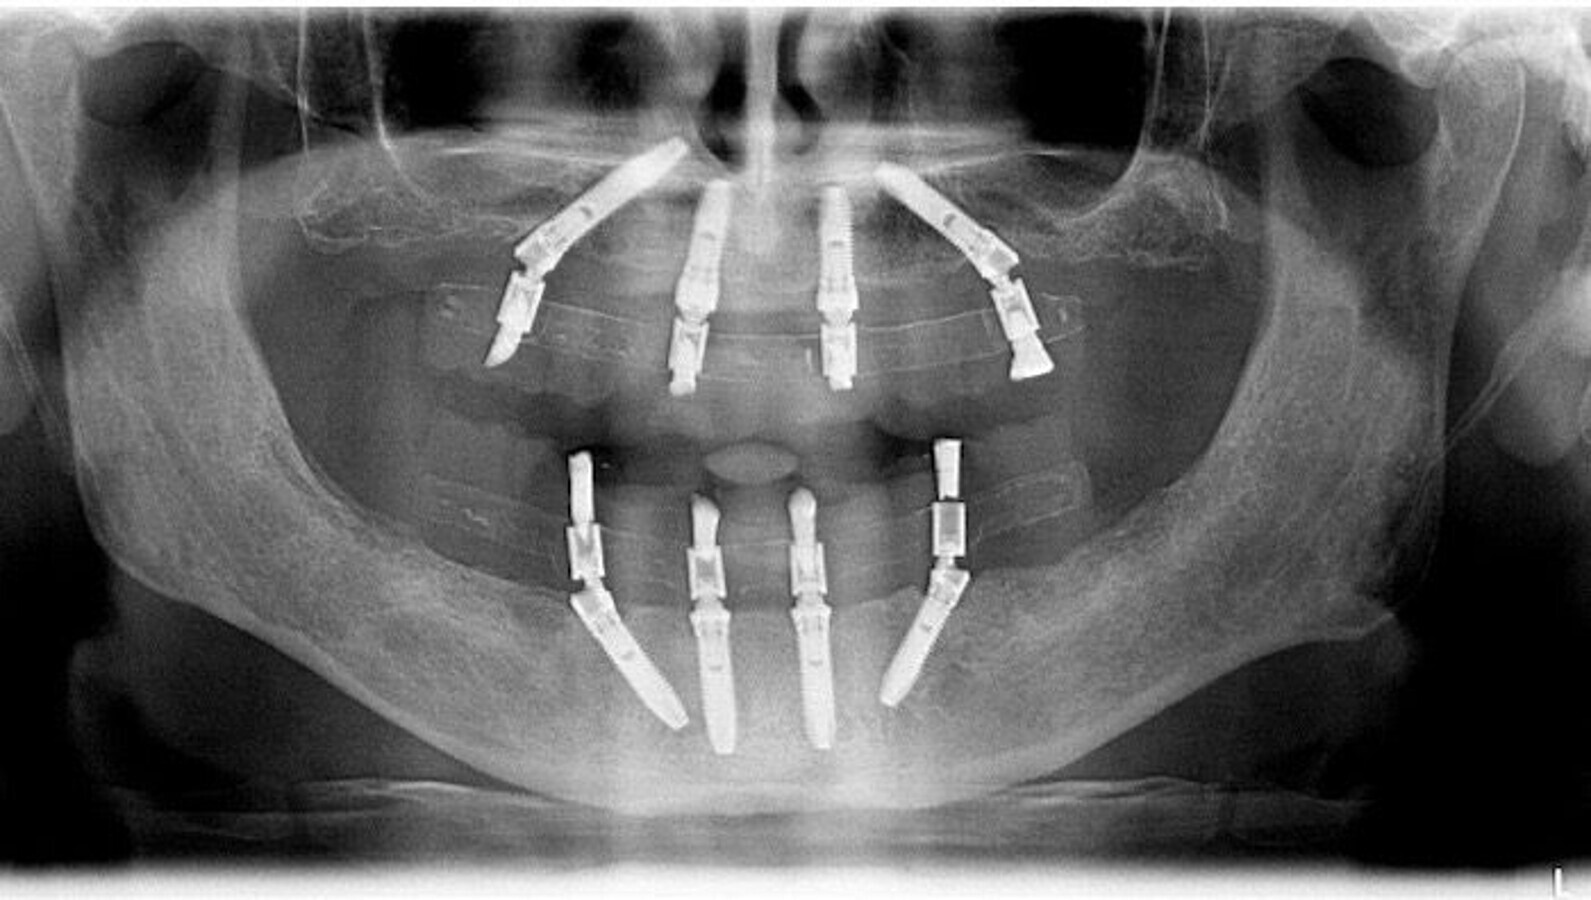

Final post-treatment orthopantomography. (Image: Miguel Nobre)